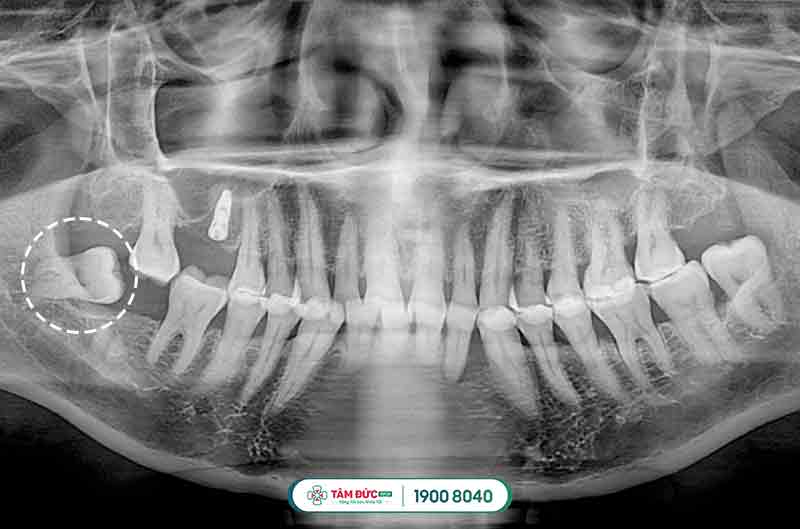

1.1 Các dạng răng khôn mọc lệch thường gặp

- Răng khôn mọc lệch má.

- Răng khôn mọc ngược vào phía xương hàm.

- Răng khôn mọc lệch và kẹt vào răng số 7.

- Răng khôn mọc ngầm trong xương hàm.

2.3.1. Tiến hành chụp phim X-quang

Chụp x-quang chiếc răng khôn mọc lệch để xác định vị trí, cũng như hướng mọc răng như thế nào rồi đưa ra phương pháp nhổ bỏ thích hợp nhất.